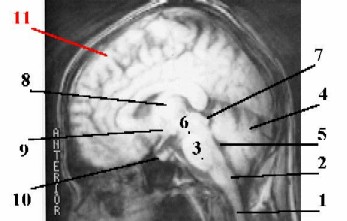

а) Итак, в головном мозгу различают 5 отделов. б) Перечислим их (и составляющие их образования), обратившись к изображениям уже сформированного мозга.

1. Продолговатый мозг (2)- это непосредственное продолжение спинного мозга (1) в ствол головного мозга. 2. а) Собственно задний мозг включает две части: варолиев мост (3) (расположенный вентрально, у основания мозга) и мозжечок (4) (расположенный дорсально). Магнитная резонансная томография (МРТ) головы.

б) Остатком полости заднего мозгового пузыря является IV желудочек (5) мозга, находящийся на уровне продолговатого мозга и мозжечка. 3. а) Средний мозг тоже имеет две части; его составляют ножки мозга (6) - проводящие пути к переднему мозгу и лежащая над ними пластинка четверохолмия (7). б) Остаток полости среднего мозгового пузыря - узкий канал, т.н. сильвиев водопровод. Схема - сагиттальный срез головного мозга человека. Полный размер

4. В промежуточном мозгу– опять-таки две части. а) Зрительные бугры (8) (в ед. числе - thalamus) - большие парные скопления серого вещества, между которыми находится полость III желудочка- остаток полости переднего мозгового пузыря.

б) Гипоталамическая область (на уровне нижних отделов III желудочка и под ним) включает высшие центры регуляции эндокринной системы - собственно гипоталамус (9) и гипофиз (10).

5. а) Конечный мозг содержит большие полушария (11) и подкорковые ядра. б) В полушариях находятся боковые желудочки, которые, как и III желудочек, происходят из полости переднего мозгового пузыря.